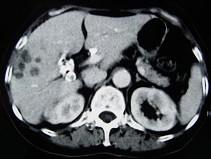

问题 女,66岁,右上腹痛,发热伴有黄疸两月余,消瘦、纳差,影像检查如图,最可能的诊断是()

选项 A.胆囊结石及脂肪肝 B.胆囊结石及肝血管瘤 C.胆囊癌肝转移 D.肝内胆管细胞癌 E.胆囊癌及原发性肝癌

答案 C